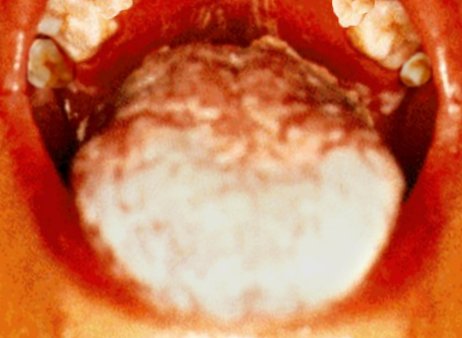

Szájpenész

A beteg szájpadlása (fent) és nyelve (lent) mutatják a szájpenészt, egy opportunista gombás fertőzést.